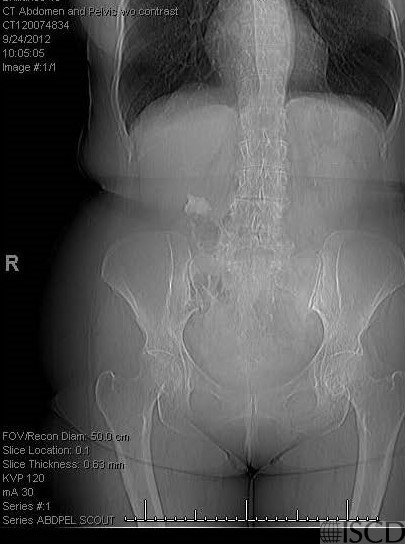

The accompany scout film from an abdominal CT scan also shows the ileostomy.